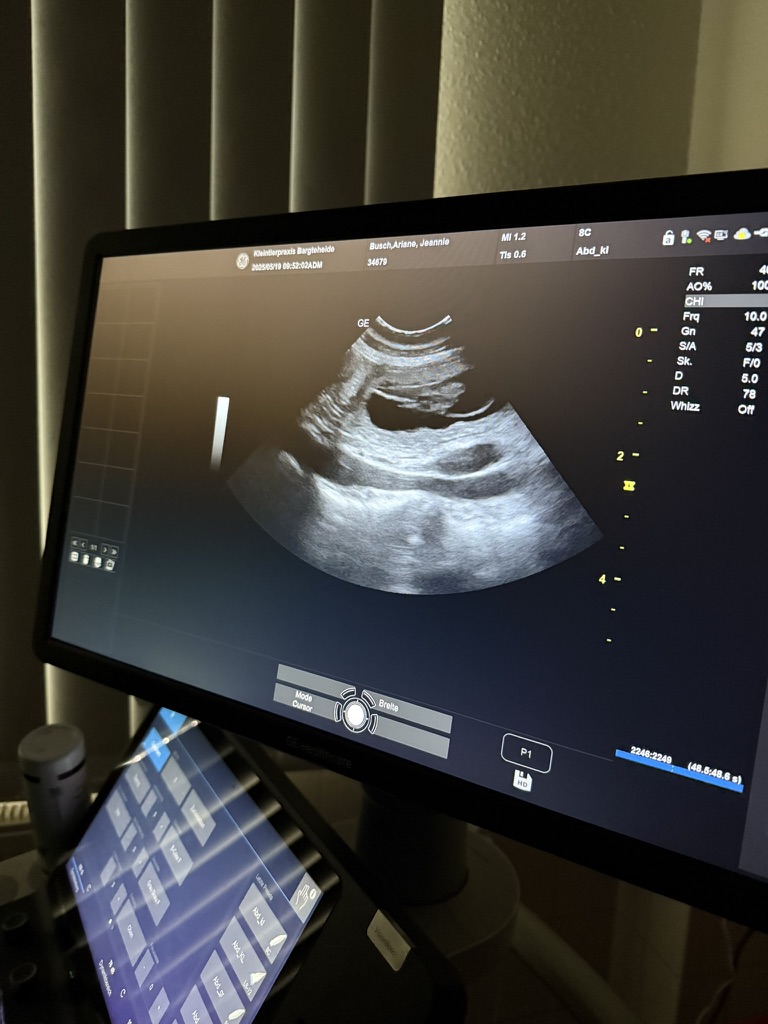

Unsere bezaubernde Jeannie „Tova‘s Riesling Surprise in Germany“ wurde Ende April von unserem charmanten Mio „Golden Nugget's Achilles“ gedeckt.